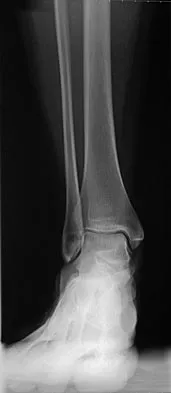

Question 10

A 29-year-old woman was injured in a high-speed motor vehicle accident 3 hours ago. Radiographs are shown in Figures 7a through 7e. Her right foot injury is open and contaminated. Her associated injuries include a closed head injury and a ruptured spleen requiring resection. She has had 6 units of packed red blood cells and the trauma surgeon has turned her care over to you. Her current base deficit is 10 and her urinary output has averaged 0.4 mL/kg for the last 2 hours. What is the best treatment at this time?